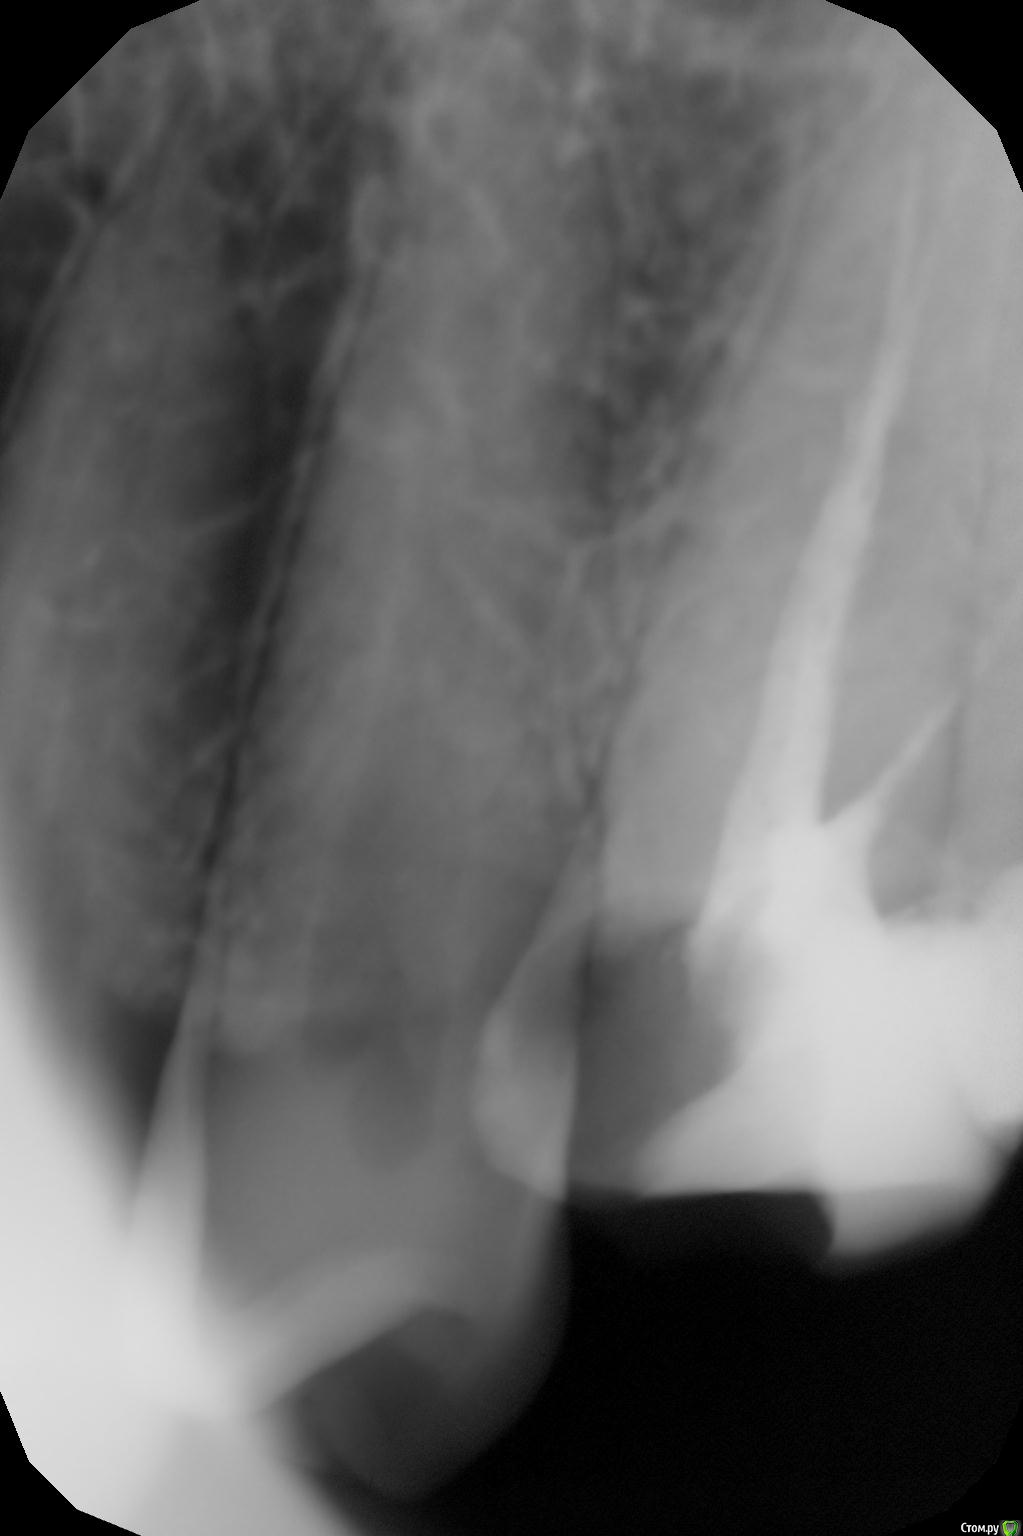

Banana Опубликовано 18 августа, 2016 Поделиться Опубликовано 18 августа, 2016 (изменено) Всем здоровья! Впервые столкнулся со стоматологическими проблемами на таком серьёзном уровне, и хотелось бы услышать мнение специалистов по поводу состояния моего зуба и того, что мне предстоит.Итак, проблема с верхней шестёркой. Анамнез. Давным-давно возник кариес, дорос до пульпита. Давным-давно обратился в государственную поликлинику. Там кариес вычистили, удалили нерв, в ходе прохождения одного из каналов допустили перфорацию, залили резорцином, сверху поставили уродливую и не функциональную светозатвердевающую пломбу. С ней я жил не тужил годы, пока не обратился за чисткой зубов в одну коммерческую клинику. Там настояли, чтобы я дал им снять пломбу, и показали, какая кошмарная чернота была под ней. Почистили, полечили. Тогда же стали проходить каналы, но прошли только три из четырёх, потому что перфорация и резорцин. К тому моменту от зуба выше десны оставались только две стеночки, и они предложили два варианта: коронка, но без всяких гарантий, что она хоть сколько-то простоит, и удаление -> синус-лифтинг -> имплантация. Про синус-лифнтинг уклончиво сказали, что по данным не ясно, понадобится ли он, и это будет видно только в ходе операции имплантации 8-мм импланта. Я выбрал последнее, поскольку это более долговечное решение проблемы. Финансовый план лечения такой:1.1 Анестезия аппликационная1.2 Анестезия инфильтрационная, проводниковая1.3 Удаление зуба сложное1.4. Закрытый синус-лифтинг (включая Bio-oss 0,25, PRP и забор материала для него)1.5. Имплантация CSM, установка формирователя десны2.1 Индивидуальная ложка2.2 Двухслойный слепок с одной челюсти (силиконовая маска)3.1 Коронка с трансокклюзией на имплант На снимках зуб до лечения и после того, как прошли три канала. На rghost выложил КТ (пароль Banana): http://rgho.st/private/8fXPD8WRy/698183a50e52bbba6e608a26d74e9344 Вопросы достопочтенной аудитории:1. Обосновано ли в данном случае удаление зуба?2. Насколько обоснован закрытый синус-лифтинг?3. Достаточно ли кости для того, чтобы провести имплантацию сразу после удаления, как и запланировано?4. К чему мне готовиться? Насколько всё плохо выглядит по снимкам? Правда ли, что после операции придётся на время исключить твёрдую пищу?5. Буду ли я играть на пианино? Всем добра! Изменено 18 августа, 2016 пользователем Banana Ссылка на комментарий

колесников Опубликовано 18 августа, 2016 Поделиться Опубликовано 18 августа, 2016 Здравствуйте!Зуб разрушен до уровня кости,герметичного соединения в этом случае не будет при реставрации. Лучше не оттягивать с удалением. Нужен ли синуслифтинг,можно ли сразу поставить имплант и формирователь-это решится в процессе удаления. Если удастся сохранить межкорневую перегородку,всё возможно. Рекомендации по уходу после имплантации даст лечащий врач ,иначе будет разноголосица. Наличие импланта не прибавляет способности играть на музыкальных инструментах. 1 Ссылка на комментарий